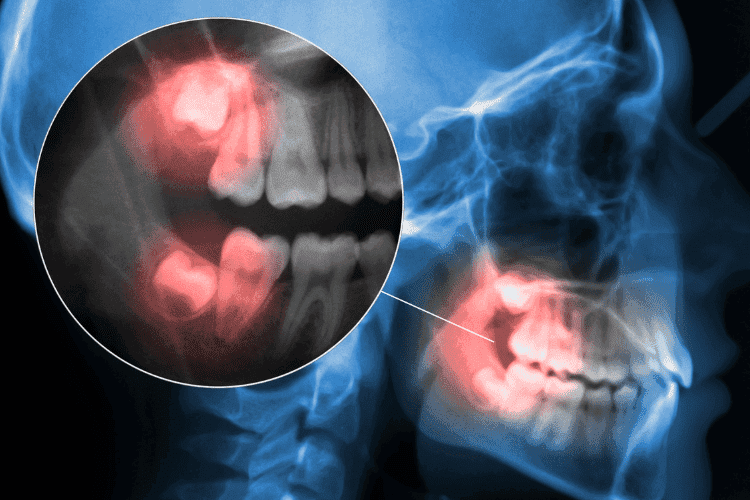

When Do Wisdom Teeth Come In? Ages, Signs & What to Expect

Wisdom teeth are the final set of molars that develop in your mouth for breaking down food. So, why do people deliberately take out their molars? Unfortunately, these teeth can be harmful to your oral health. Learning more about wisdom teeth can help you determine if...

The Worst Day of Pain After Wisdom Tooth Extraction: What to Expect

Wisdom tooth extraction is a common dental procedure. It involves removing one or more of your third molars. These are the last teeth to come in your mouth. They often cause issues like crowding, impaction, or infection due to limited space in the jaw. Recovery from...